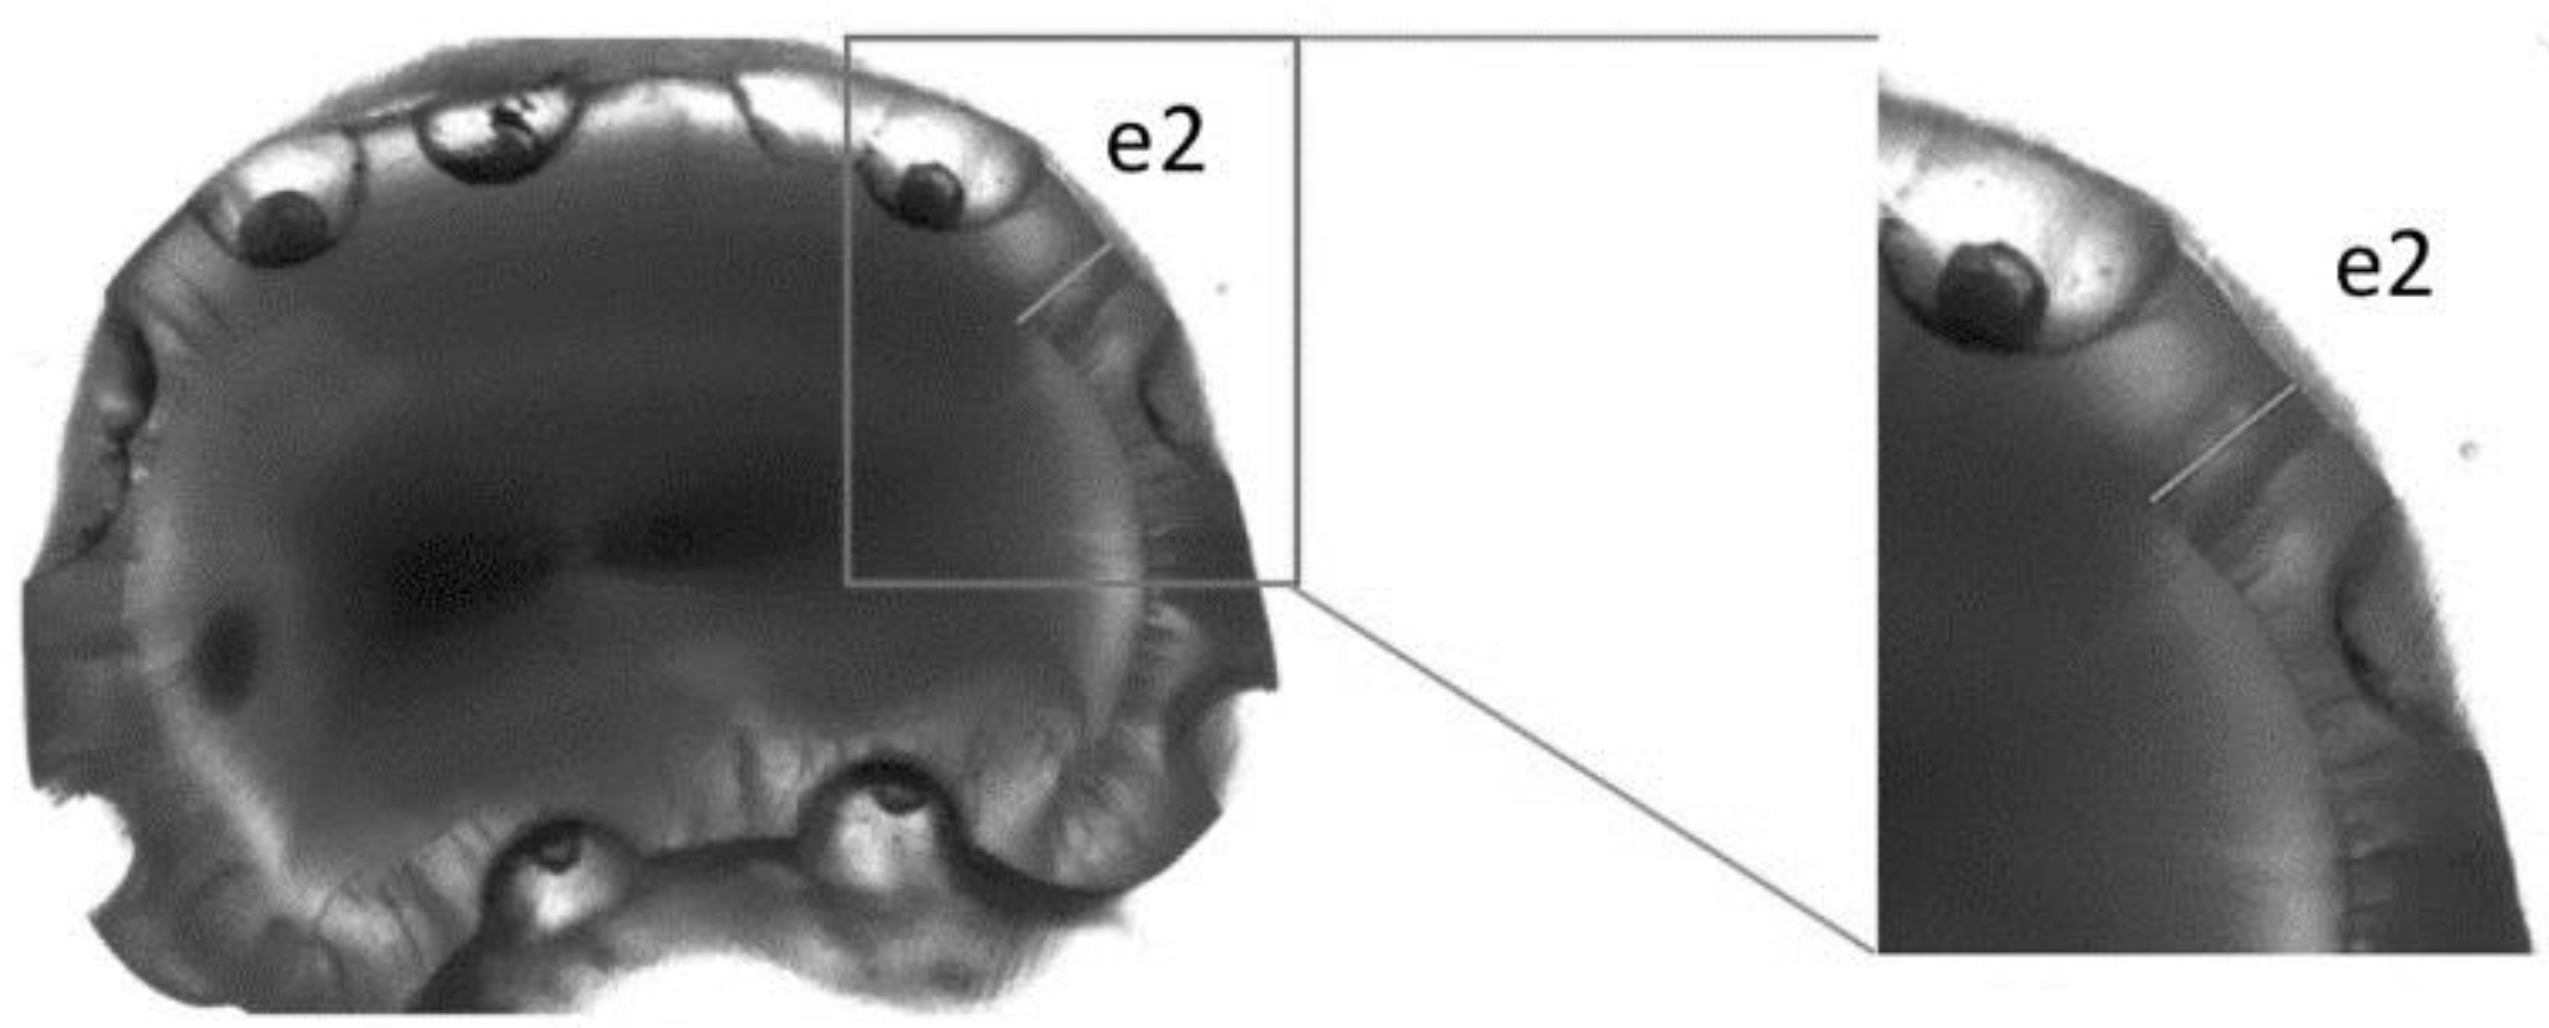

2.1. Specimen Preparation

2.4. Light Microscopy Measurements